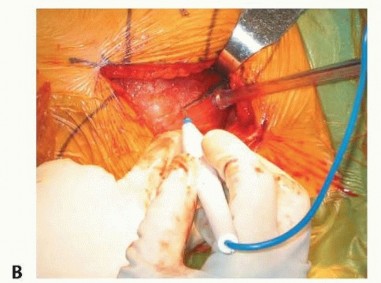

صورة طبية: نصف مفصل الورك: دليلك الشامل لدواعي الاستخدام والأنواع في صنعاء